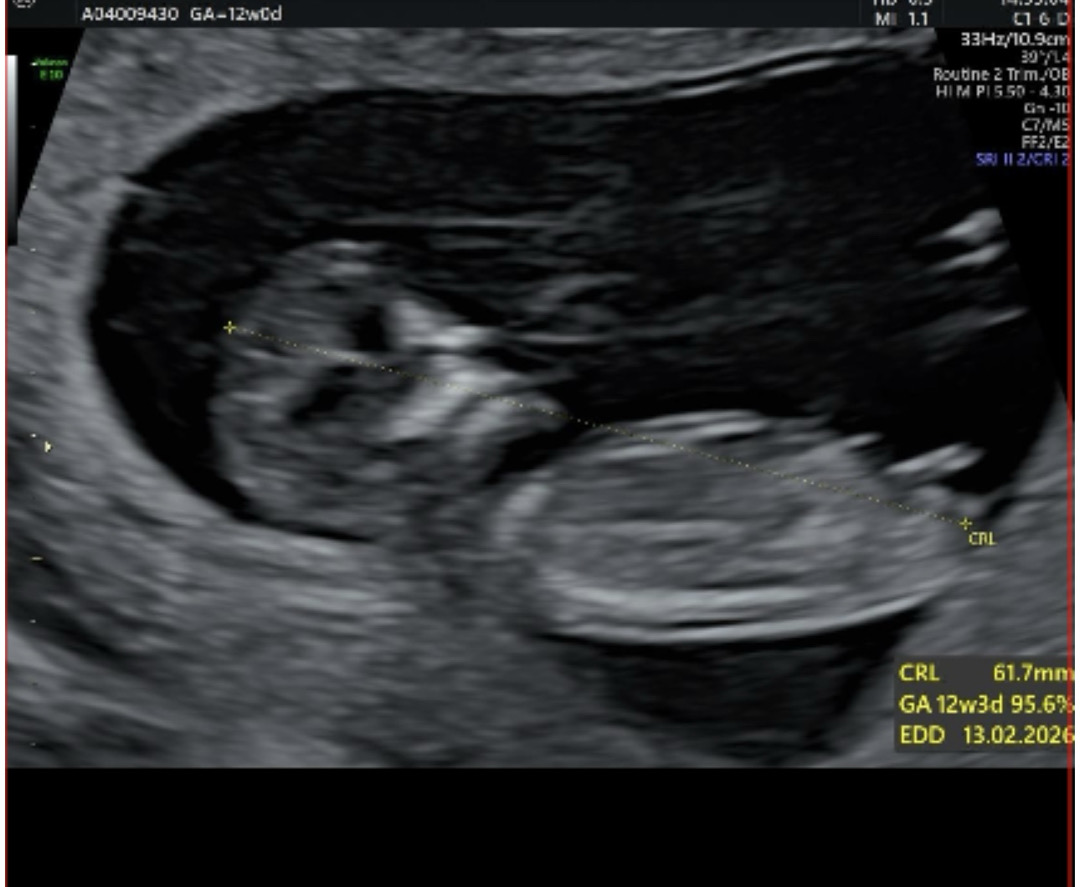

안녕하세요! 해외사는 12주차 산모입니다 ㅎㅎ 오늘 nipt하면서 초음파 한번 봤는데, 성별 결과는 7-8일 걸린다구 하더라구요!! 혹시 아들인지 딸인지 한번 봐주시면 감사하겠습니다!

각도는 딸인것같아용